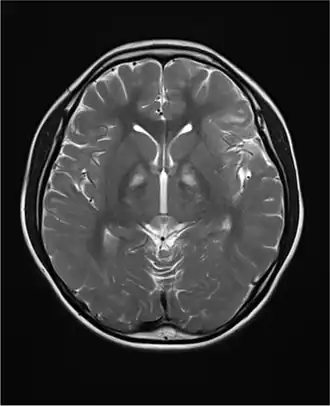

Het syndroom van Kearns-Sayre[1] (KSS) is een zeldzame (ca. 1:600.000) energiestofwisselingsziekte. De ziekte hoort ook thuis in de groepen mitochondriële ziekten en spierziekten. Het syndroom werd voor het eerst beschreven in 1958 door de Amerikaanse oogartsen Thomas P. Kearns (1922-2011) en George Pomeroy Sayre (1911-1992).

Verschijnselen

De verschijnselen van patiënten met mitochondriale ziekten zijn enorm divers. Dit komt doordat mitochondriën in alle cellen voorkomen. Zodra er in deze cellen een energiecrisis ontstaat leidt dit tot het slecht werken van deze cellen. Wel is het zo, dat vooral die weefsels waarin veel mitochondriën in de cellen voorkomen omdat zij veel energie nodig hebben, het meest frequent klachten geven. Bij het syndroom van Kearns-Sayre zijn de klachten vaak spierklachten, hartklachten, hangende oogleden, hersenfunctiestoornissen leidend tot geestelijke achterstand, bewegingsstoornissen en soms zelfs epileptische aanvallen.